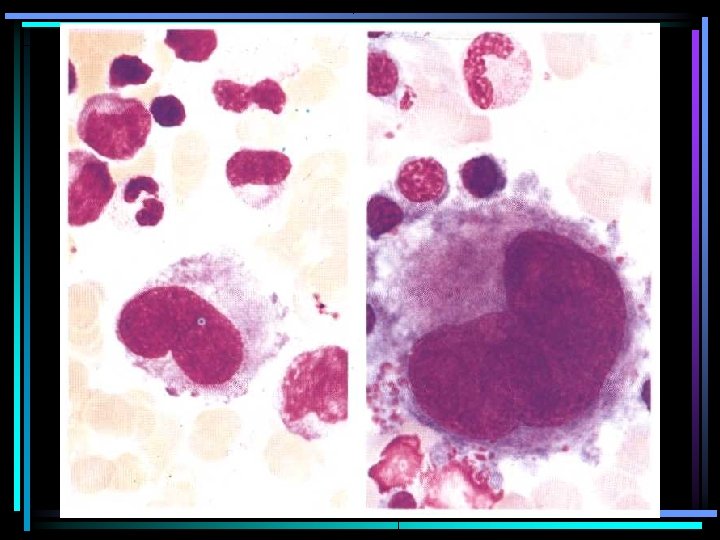

Monosit

PMN lökosit ve Monosit